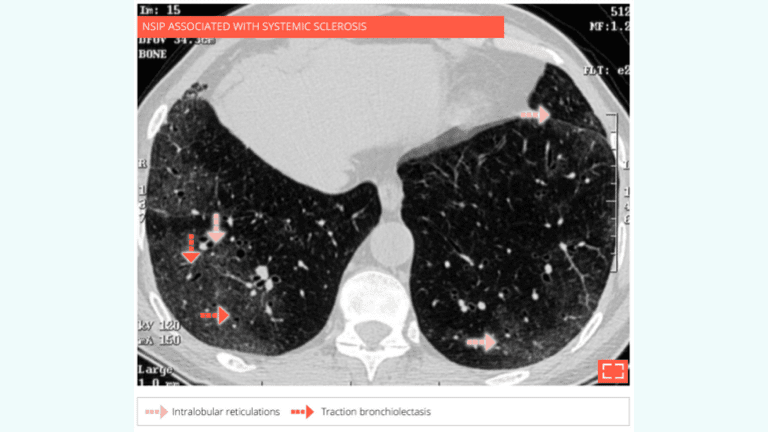

4. Ground-glass opacity associated with intralobular reticulations and traction bronchiolectasis

• Radiological pattern consistent with NSIP.

• No honeycombing.